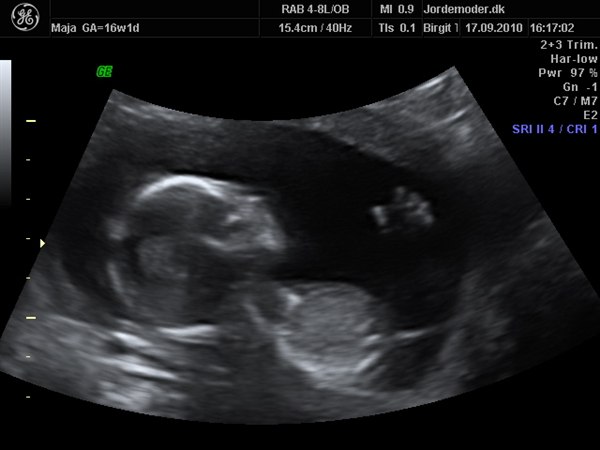

Vi var i fredags til scanning hvor jeg var 16+1 og det var en super fed oplevelse, selvom den lille var genert

vi ønsker ikke at vide kønnet, så er jo dejligt vi alligevel kunne få lov at opleve 3D

Vedhæftede fotos (klik for at se i fuld størrelse)